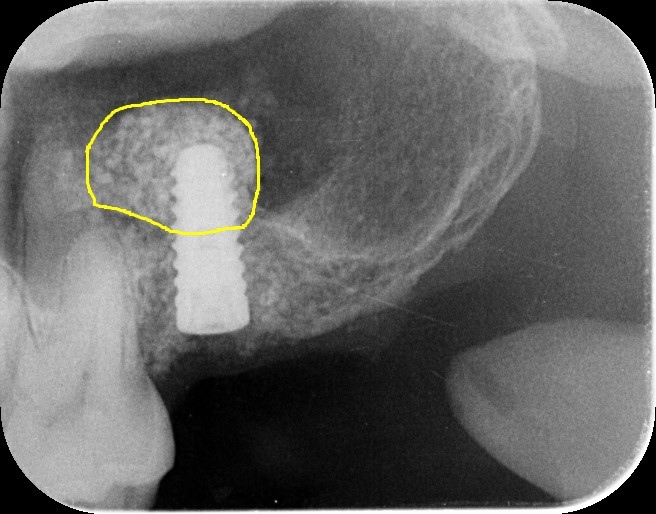

本日は腫れないサイナスリフト ラテラルスリット法を行いました アテラルスリットは、笹尾歯科医院オリジナルオペ手法です。 治療内容 ラテラルスリット 性別 男性 31歳 治療期間 6か月 治療費 20万円 治療で得られるメリット 奥歯…